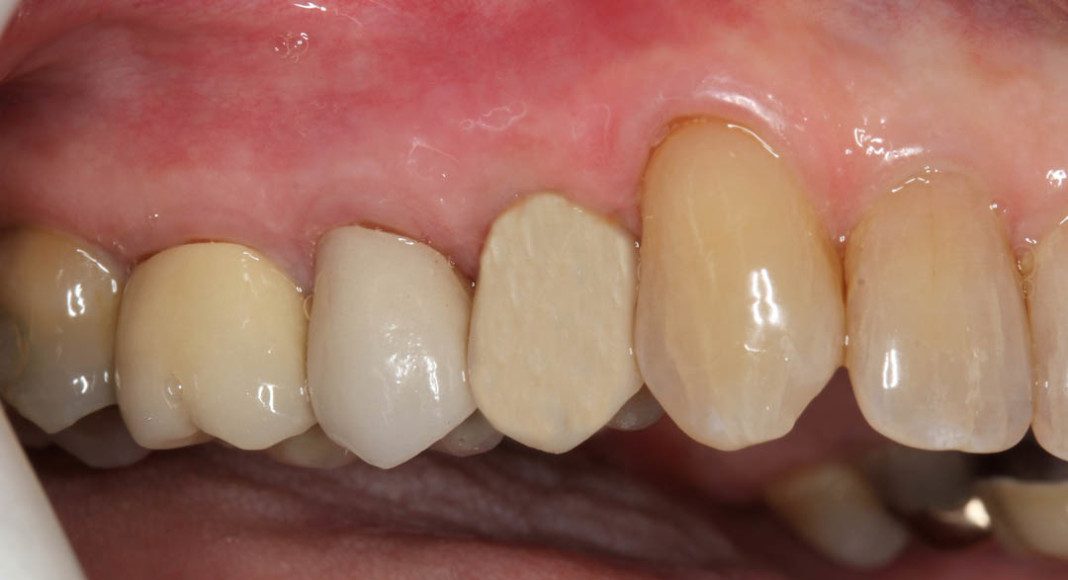

Though not obvious on the x-ray, this patient has fractured his upper right 1st premolar. Treatment plan: Extract tooth, place implant, fabricate an immediate, screw retained, temporary implant crown. Patient will never need to wear a removable partial or go without a tooth.